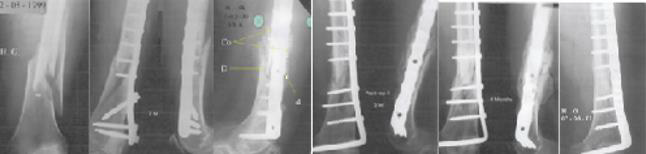

Radiographic Evolution of the Femur of the Young Patient

Here in this section, we go over the evolution (from 0 to 20 months) of the reconstructed bone of the 19-years-old patient. The radiograph story presented in Figure 11 depicts the new internal fixation and bone consolidation after 4 months. The reader can find in the following table1 the different stages of this remarkable reconstruction.

Figure 11: Non-union of a femoral shaft (at 7 months) taken over by a new osteosynthesis and a coral graft. Bone consolidation is seen after 4 months.